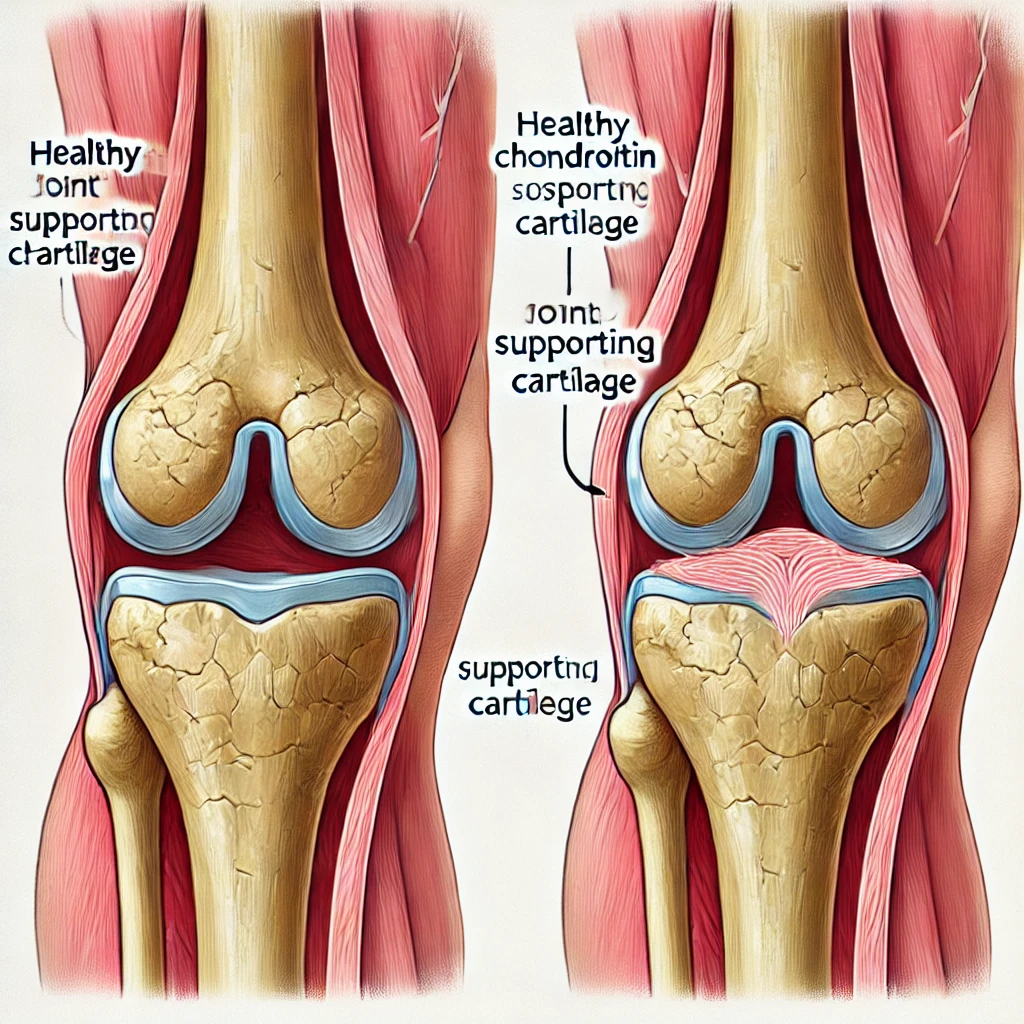

연골 보호 및 재생

콘드로이친은 연골을 구성하는 중요한 요소로, 손상된 연골을 회복시키는 데 도움을 줍니다. 이를 통해 관절의 마모를 줄이고, 관절염과 같은 질환을 예방하는 역할을 합니다.

연골 손상 방지

장기적으로 사용하면 연골 손상을 방지해 관절 질환의 진행을 늦추는 데 도움이 됩니다. 만성적인 관절염 환자들에게 유용할 수 있습니다.